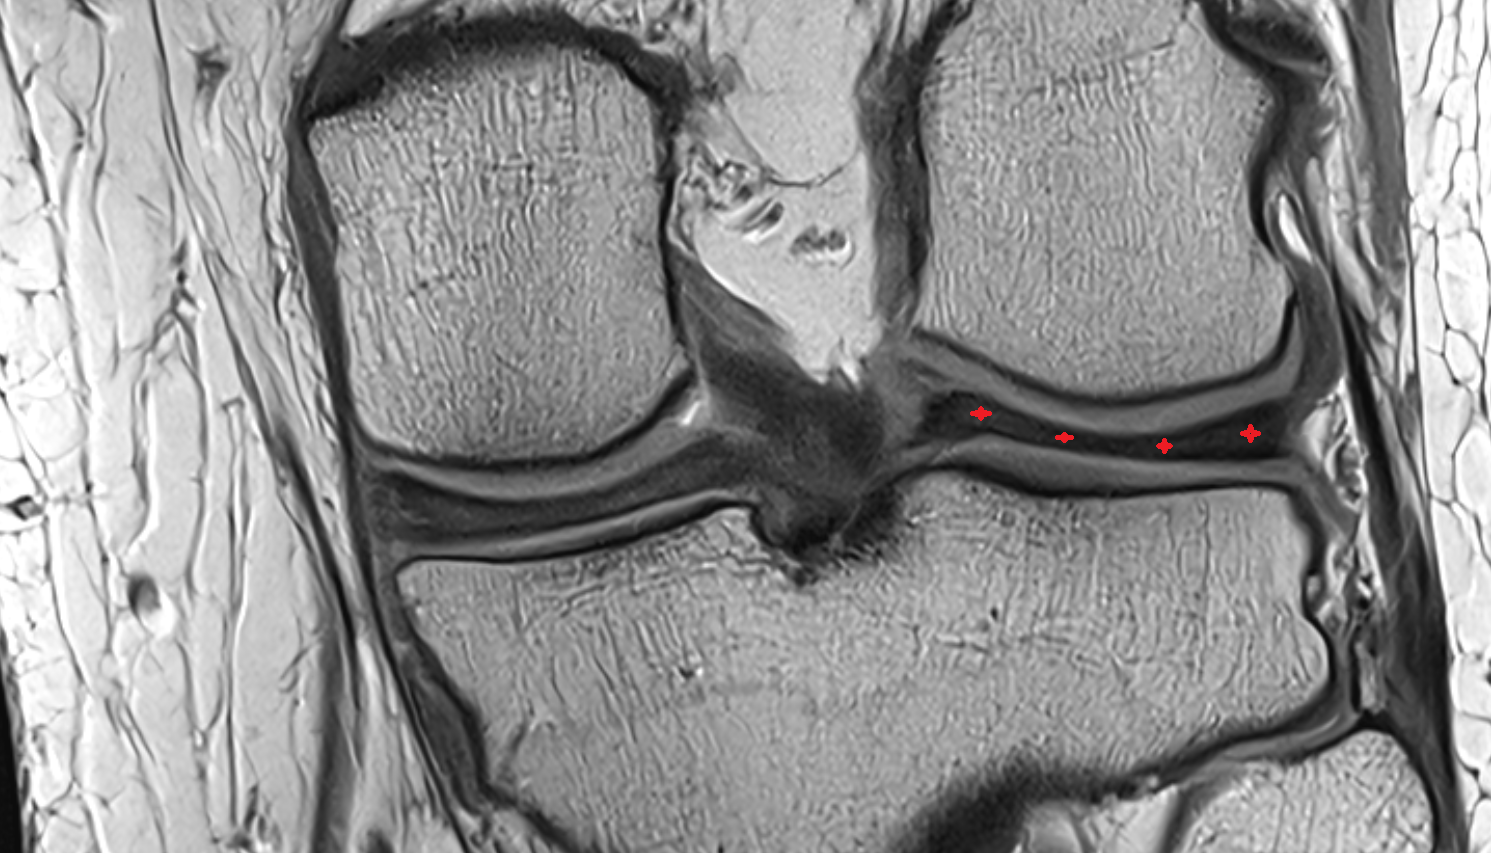

- Medial collateral ligament

- Lateral collateral ligament

- Medial meniscus

- Lateral meniscus

- Knee Joint